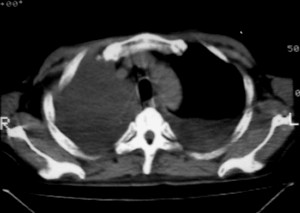

m ,60岁,右上肺ca术后一月。

纵隔淋巴结增大,双侧胸水。考虑术后残留,而非复发。

肺癌术后 。双侧胸水 纵隔 胸膜 肝脏转移